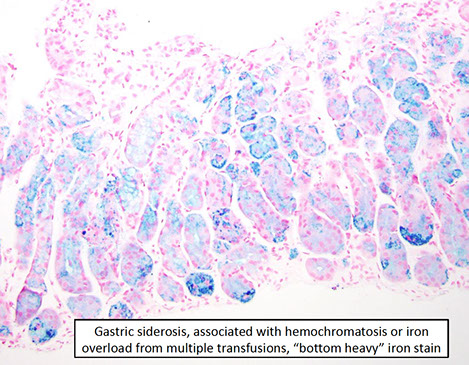

Iatrogenic injury / Chemical injury

Iron

Relatively common; usually in concert c some other dz process

- can have iron thrombi; has similar appearance as iron esophagitis

- may have severe changes that mimics carcinoma

- systemic iron overload (siderosis) is more rare and may cause changes in deep gastric glands

Iron pill gastritis with severe reactive epithelial changes [1]

gastric siderosis [1]

Gastric siderosis, iron stain [1]